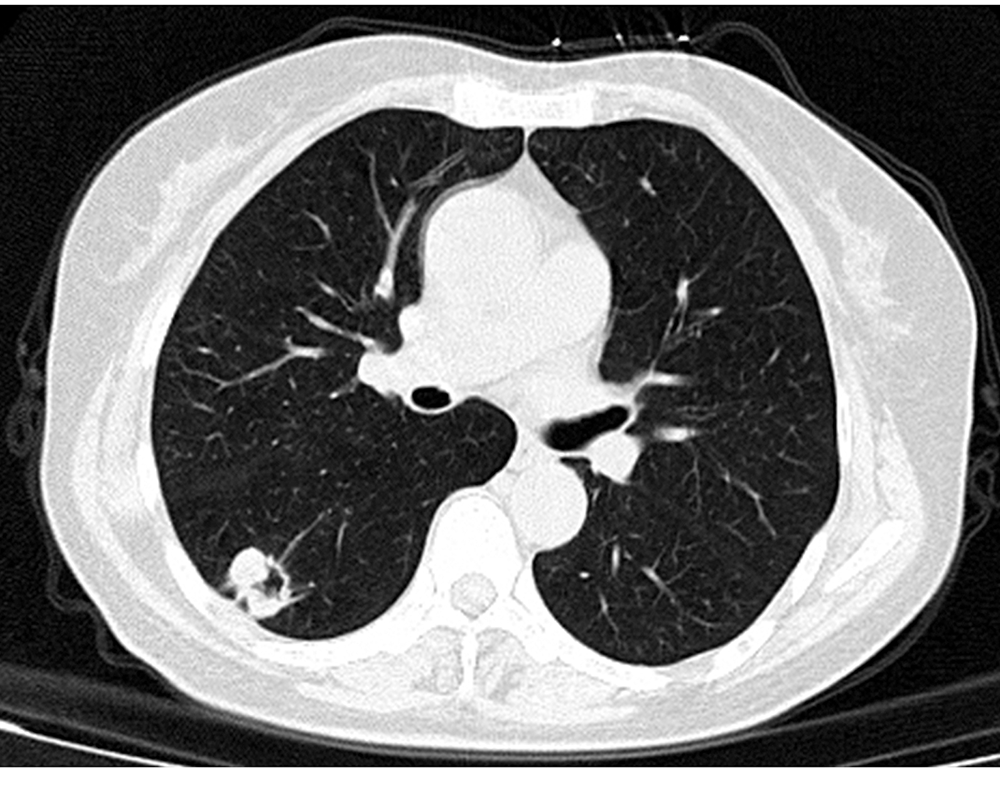

摘要:

ObjectiveTo investigate the correlations between multi-slice spiral CT (MSCT) atypical pleomorphic signs and pathological findings of lung metastases.MethodsFrom January 2012 to July 2019, the MSCT chest imaging data of 168 metastatic tumor of lung from the General Hospital of Central Theater Command of the Chinese People's Liberation Army and Shaanxi Provincial Tumor Hospital were collected. According to the pathological type, they were divided into metastatic adenocarcinoma group (n=88) and metastatic squamous cell carcinoma group (n=80). The atypical imaging signs of MSCT of the two groups were observed and recorded, and classified after labeling one by one. The difference of atypical MSCT imaging features between the two groups was compared, and the correlations between lesion size and atypical imaging features of MSCT in the metastatic adenocarcinoma group and metastatic squamous cell carcinoma group were analyzed.ResultsThe spicule sign in metastatic adenocarcinoma and metastatic squamous cell carcinoma were 61 (69.32%) and 28 (35.00%), with a statistically significant difference (χ2=19.811,P<0.001). The pleural depression sign in the two groups were 48 (54.55%) and 16 (20.00%), and there was a statistically significant difference (χ2=21.206,P<0.001). The vacuole/cavity sign in the two groups were 10 (11.36%) and 61 (76.25%), and there was a statistically significant difference (χ2=72.303,P<0.001). The air bronchial sign in the two groups were 43 (48.86%) and 13 (16.25%), with a statistically significant difference (χ2=20.057, P<0.001). The halo sign/ground glass shadow in the two groups were 58 (65.91%) and 37 (46.25%), with a statistically significant difference (χ2=6.591,P=0.010). The results of the Spearman rank correlation analysis indicated a positive correlation between the size of metastatic adenocarcinoma and spicule sign, pleural depression sign (r=0.270,P=0.011;r=0.226,P=0.035). There was no correlation between the nodule size and atypical MSCT imaging features in metastatic squamous cell carcinoma (allP>0.05).ConclusionThe atypical MSCT of metastatic lung adenocarcinoma are mostly spicule sign, pleural depression sign, air bronchial sign and halo sign/ground glass shadow. The characteristic atypical imaging of metastatic squamous cell carcinoma is vacuole/cavity sign. The spicule sign and pleural depression sign are related to the size of metastatic lung adenocarcinoma nodules.